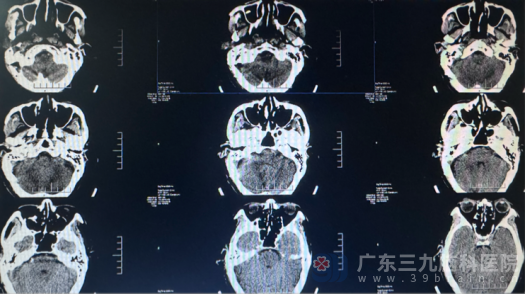

马大爷的情况在三叉神经痛患者中颇具代表性。这种被称为“天下第一痛”的疾病,发作时如同刀割、电击剧痛感觉,常因咀嚼、洗脸等日常动作诱发。马大爷曾尝试服用卡马西平缓解症状,但随着时间的推移,药物效果逐渐减退,疼痛却日益频繁。马大爷在家人的陪伴下来到我院神经外十科。经过详细检查,马大爷被诊断为“右侧三叉神经痛”,林德留副主任将患者收住院。

鉴于马大爷复杂的身体状况,治疗团队为他提供了四种治疗方案:三叉神经微血管减压术、微球囊压迫术、射频消融术以及单纯的药物治疗。经过详细沟通和评估,考虑到马大爷的年龄和基础疾病状况,团队最终选择了微血管减压术——这是目前唯一能从病因上治疗三叉神经痛的方法。